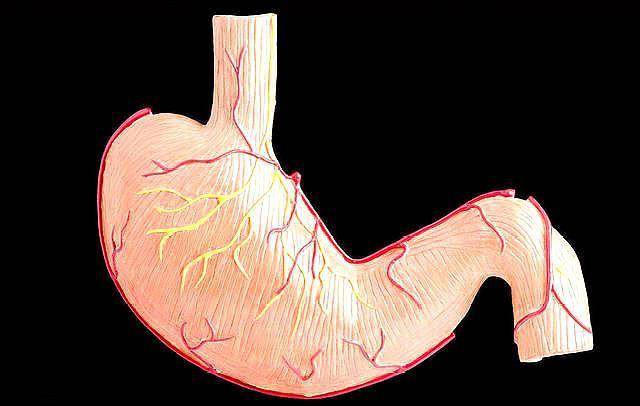

【科普帖】图解胃癌发展四阶段

胃癌的发展分为四个阶段,因为这个胃壁是分为五层的,胃癌一阶段,癌组织起源粘膜的上皮组织,在胃粘膜下,这个叫做“早癌”,这个阶段,癌组织没有突破胃粘膜,这个时候癌组织就是米粒大。

然后会尽一步发展为胃癌二阶段,癌组织由米粒大又变大了一点点,但是还是没有突破肌层,在“早癌“出现,到二阶段,因为癌组织还没有突破肌层,所以人是没有任何主观感觉的,只能靠“胃镜”发现,所以只能靠自己主动去检查。这个阶段能及时处理,基本都可以痊愈。

如果很倒霉的没有及时发现,那么就会进入三阶段,癌组织发展成绿豆或花生米那么大了,这时癌组织已经到了胃粘膜的底层,就快到达外面了,胃的周围开始出现淋巴节转移,癌组织可以通过淋巴网,到处跑,这个阶段是癌组织转移前段准备,三期也叫做“进展期”,这个阶段有明显的主观感觉了,这个阶段处理的方法一般都是手术、化疗,这个阶段痊愈的成功率只有四、五成,在这里向大家科普一个概念:目前癌症的治愈标准是“五年内不复发”,也就是说如果你得了胃癌,及时处理了,五年都没有复发,那么这一次抗癌就成功了,如果是五年后,再长又或者是其他癌,那就属于新一次的抗癌,不叫复发。

三阶段控制失败,那就进入四阶段,这个时候的癌组织已经有核桃大了,不但把胃壁侵占了,还侵出来了,严重影响其他器官,远的可以到肺,颈部淋巴结。到了这个阶段,只能指望有“奇迹”,基本都是人财两空!